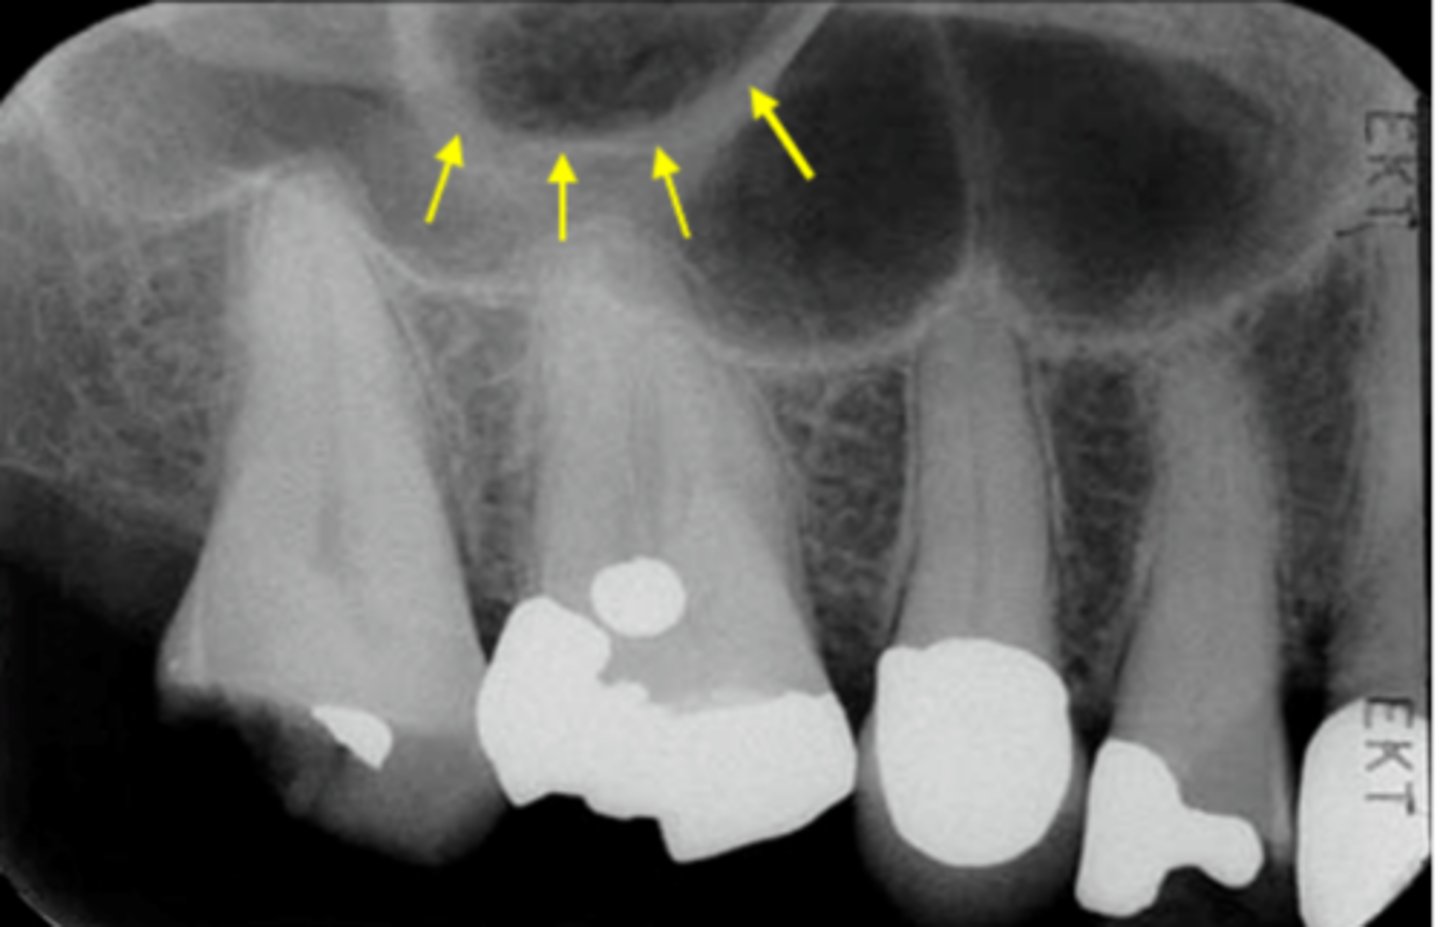

7

New cards

Name the curved, radiopaque structure indicated by the arrows.

<p>Name the curved, radiopaque structure indicated by the arrows.</p>

What does the line indicated by the arrows represent?

<p>What does the line indicated by the arrows represent?</p>